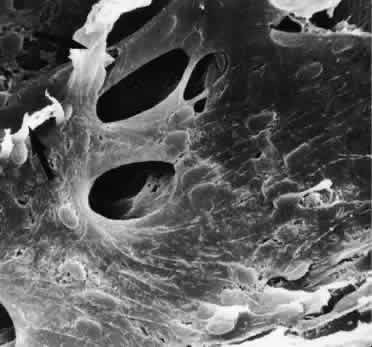

Scanning electron micrographs of serial layers through the entire meshwork and tangential sections (parallel to the inner wall of Schlemm's canal) reveal that the form of the trabecular lamellae and of the intertrabecular spaces changes markedly from the inner to the outer portions of the meshwork. The innermost iridial meshwork consists mostly of long, radial, interconnecting strands forming an irregularly arranged network with rather large openings (Figs. 3 and 4). In the uveal portion, flat sheets are evident that are still relatively irregularly arranged but frequently interconnect with each other. The holes within the uveal meshwork are somewhat smaller than in the iridial meshwork but still show diameters varying between 10 and 30 μm.

Toward Schlemm's canal the corneoscleral meshwork is more expanded and forms broad lamellae that run predominantly in an equatorial direction (Fig. 5). The trabecular lamellae interconnect with each other and are regularly arranged. The intertrabecular spaces appear now as elongated rhomboid-like pores, the long diameter of which averages 10 to 20 μm.7